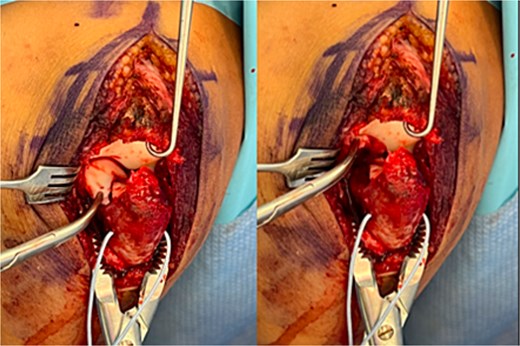

Surgical fixation was performed through a posterior approach. A large cartilaginous fragment involving the trochlear notch and coronoid articular surface was identified, lacking substantial subchondral bone (Fig. 3). The fragment was anatomically reduced using a mosquito clamp and fixed with three bioabsorbable chondral fixation darts. The olecranon fracture was stabilized with two Kirschner wires and a tension-band construct. Intraoperative fluoroscopy confirmed satisfactory alignment. The elbow was immobilized in a long arm cast in slight extension.

Intraoperative photographs showing a large chondral shear fragment involving the trochlear notch, visualized prior to reduction.